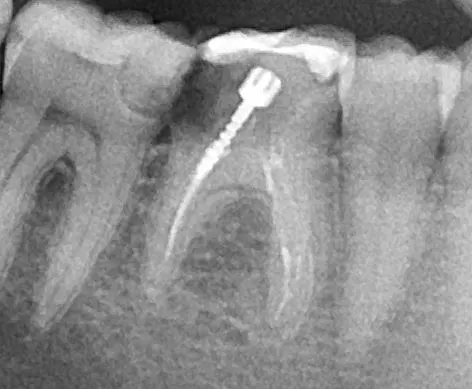

Снимка

преди